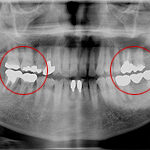

インプラントによる噛み合わせの回復

治療前 初診のレントゲンです。 向かって左下の歯は根が割れてしまい根の周囲が黒く ...